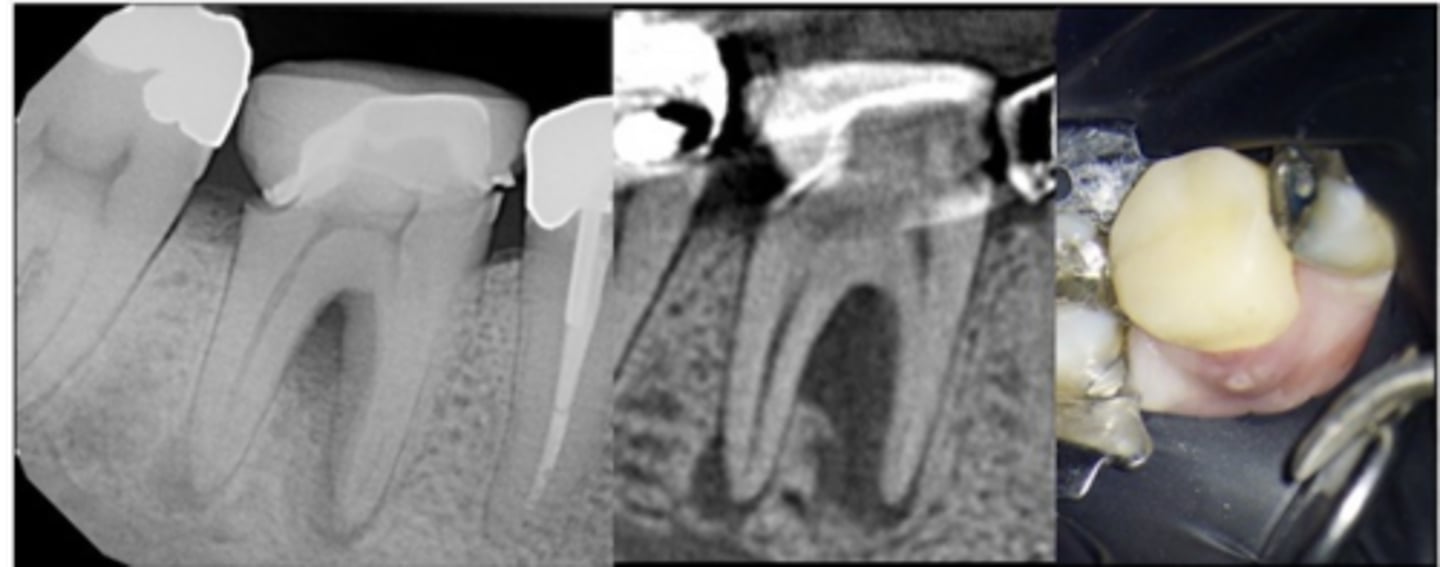

Could this be a vertical root fracture or a crack?

- Tooth #30 CC: “There’s a bump on my gums”

- Sinus tract near B sulcus

- Probing: 12mm MB, 7mm B

- CBCT shows furcation bone loss joining with PARL at M apex; separate PARL at D apex; crestal bone appears WNL

- Pulpal dx: Necrotic

- Periapical dx: Chronic apical abscess

No (because it is not previously treated)

What type of lesion?

- Tooth #30 CC: "There's a bump on my gums"

- Apical and furcal bone healing observed at recall without additional periodontal treatment

Primary endo with secondary perio lesions